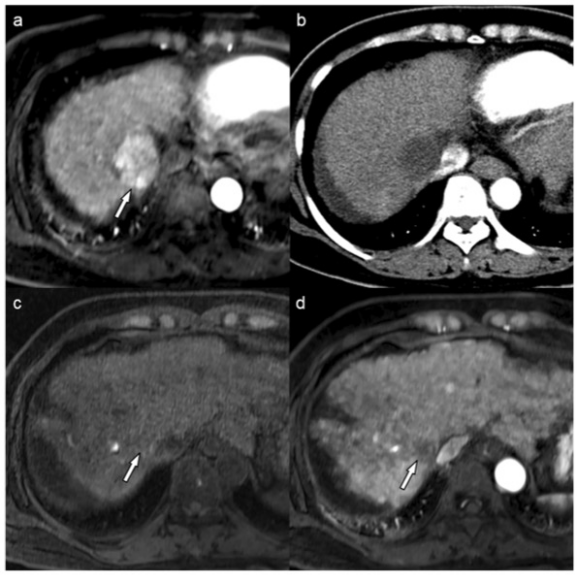

圖 50歲女性肝細胞癌(HCC)的MR和CT圖像。動脈期MR圖像顯示肝臟第7段有一個4.2厘米的HCC(箭頭)(a)。經過一個療程的藥物洗脫珠-TACE治療后,患者獲得了持久的影像學完全反應(b)。肝移植時,對比前(c)和動脈期(d)的MR圖像將目標病變分配為LR-TR非生存類別(箭頭)。術前血清AFP水平為3.3納克/毫升。風險評分為0,患者屬于有利的風險組。手術后,證實了病理上可行的腫瘤,60%的腫瘤已經壞死?;颊咴谛g后104.6個月內一直存活且無復發